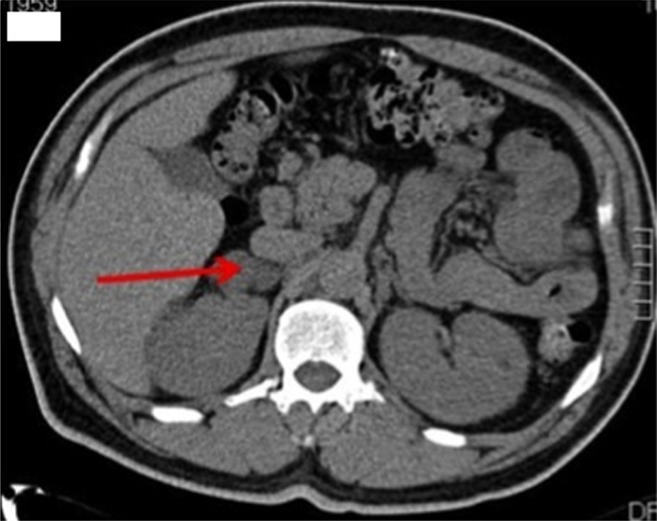

Results: A patient presented with hypertension, hypokalemia, and symptoms related to hypercortisolism. The case demonstrated suppressed renin concentrations with an elevated aldosterone:renin ratio, abnormal dexamethasone suppression test results, and elevated midnight salivary cortisol concentrations. The patient had a right adrenal nodule with autonomous cortisol production and interval growth. Right adrenalectomy was carried out. Postoperatively, the patient tolerated the surgery, but he was placed on a short course of steroid replacement given a subnormal postoperative serum cortisol concentration. Long-term follow-up of the patient showed that his blood pressure and glucose levels had improved. Histopathology slides showed positive staining for 3β-hydroxysteroid dehydrogenase, 11β-hydroxylase, and 21 hydroxylase.